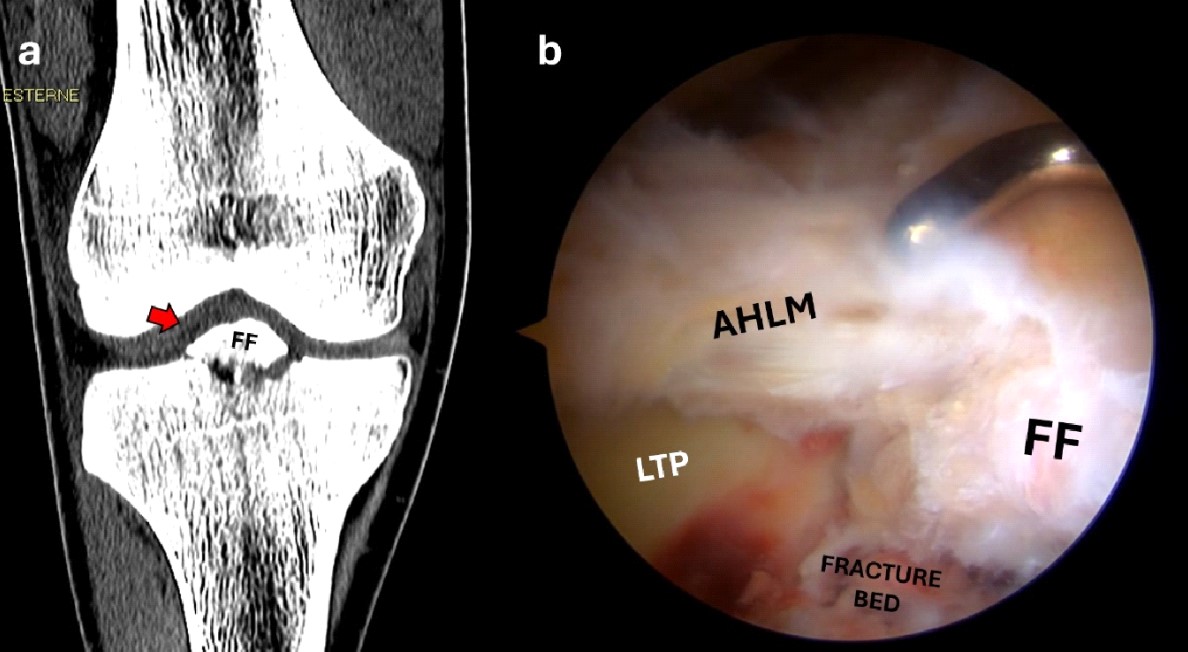

When enough visibility is obtained, the intraarticular hematoma is aspirated using a shaver through the anteromedial portal. During this stage, the ligamentum mucosum and part of the infrapatellar fat pad are resected to allow adequate visualization. After the hematoma has been evacuated, it is possible to inspect the joint for any other intra-articular lesions that should be addressed (Figure 2b, c). Care should be taken to check the condition and integrity of the anterior cruciate ligament (ACL) and the status of the articular cartilage and menisci, especially the anterior root of the lateral meniscus that could be avulsed with the spine. In this case, the anterior root of the lateral meniscus could displace the fracture fragment laterally and proximally (Figure 3). The fragment and its bony bed should be gently freed from hematoma and fibrous tissue to allow the study of the fracture pattern, keeping in mind the preoperative radiological exams. If the fracture is comminuted, small fragments (1-2 mm) should be removed to avoid producing loose bodies (Figure 4).

Figure 3. Coronal CT scan showing an anterior eminence fracture (red arrow) displaced laterally and proximally (a); the arthroscopic view shows connection of the anterior horn of the lateral meniscus with the main fracture fragment (b).

FF, fracture fragment; LTP, lateral tibial plateau; AHLM, anterior horn of the lateral meniscus.